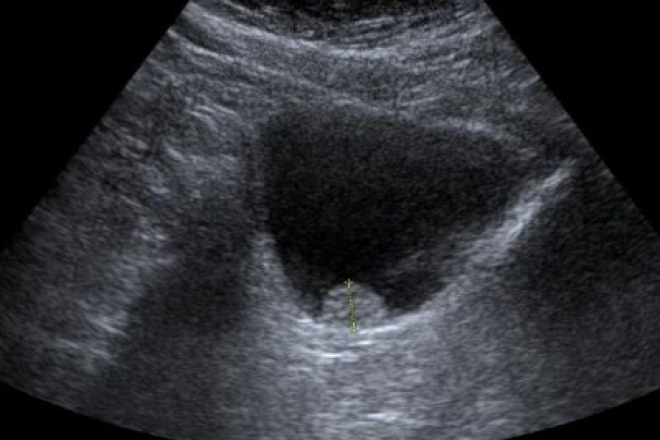

El ultrasonido transrectal es una herramienta clave en los estudios de imagen para la detección del cáncer de próstata. Permite visualizar las zonas ecogénicas de la glándula y detectar posibles lesiones sospechosas, que suelen ser hipoecoicas.

La evaluación ecográfica puede revelar hallazgos como asimetrías, hipervascularidad, hipoecogenicidad, protuberancias e irregularidades en la próstata, que están asociados con la presencia de cáncer.

El USG transrectal es útil para identificar lesiones en áreas específicas como los cuernos posterolaterales, la base de la próstata y el ápex.